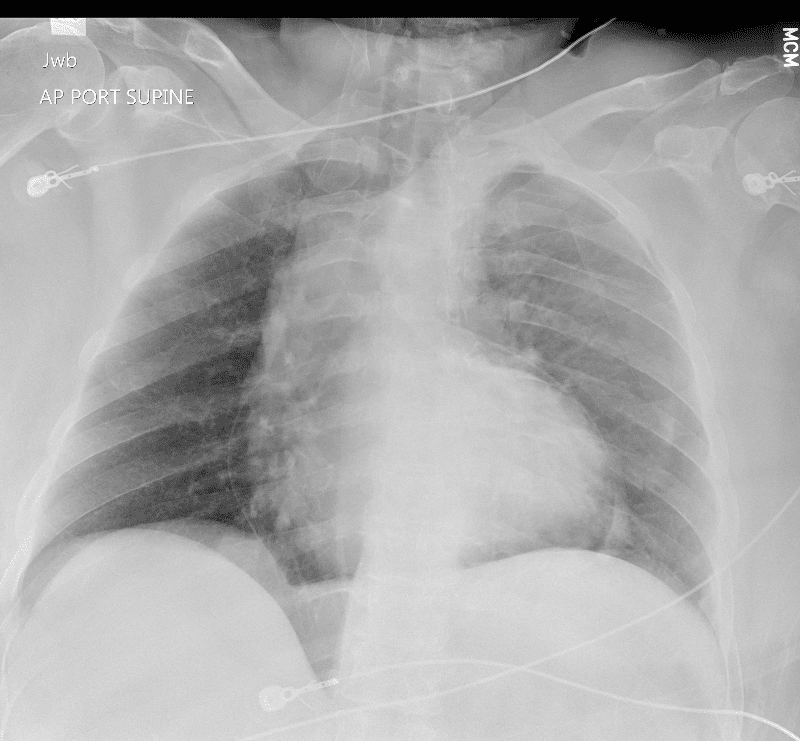

Practice Cases